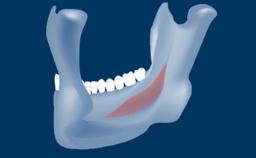

This learning module will provide an overview of the most commonly seen intraoperative and postoperative complications associated with sinus floor elevation and will discuss management in terms of preventative measures as well as treatment strategies.

• intraoperative complications of lateral window sinus floor elevation

• intraoperative complications of transcrestal sinus floor elevation